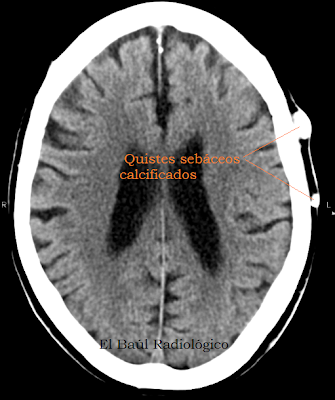

Uno de los hallazgos más frecuentes en las exploraciones de Tomografía Computarizada o Tomografía por Resonancia Magnética (TRM) craneoencefálicas son los quistes sebáceos del cuero cabelludo. Algunos los confunden con osteomas, pero son cosas completamente distintas y su repercusión patológica también. Los quistes sebáceos pueden formarse en la piel de cualquier parte del cuerpo. Son nódulos duros, desplazables porque no están adheridos a estructuras profundas. Se originan en la dermis, en la base de un folículo piloso. Rodeados por una cápsula, contienen restos de tejidos cutáneos, conglomerados de queratina y calcificaciones grumosas que les confieren el aspecto hiperdenso en las imágenes de Tomografía Computarizada (Figura 1). Son de morfologia redondeada, están en contacto con el hueso, pero no dependen de él como los osteomas que se originan en el hueso compacto cortical y tienen una base de inserción plana. Los quistes sebáceos son siempre benignos y no se extirpan, salvo por problemas estéticos.

(One ofthe most common findings, onCT scansorcraniocerebralMRI images,are sebaceous calcified cystsof the scalp.Some radiologistsconfuse themwithosteomas,but they arecompletely different thingsand itspathologicalimpactas well. We present some cases of sebaceous calcified cysts of the scalp)

FIGURA 2) Imagen axial de TC craneo-encefálica en la que se observan dos quistes sebáceos calcificados del cuero cabelludo. Es un hallazgo muy frecuente y no deben ser etiquetados de osteomas.

(AxialCTimagein which we can appreciate, in the scalp, twocalcifiedsebaceous cysts. It is avery common findingand they should not beconfusedwithosteomas)